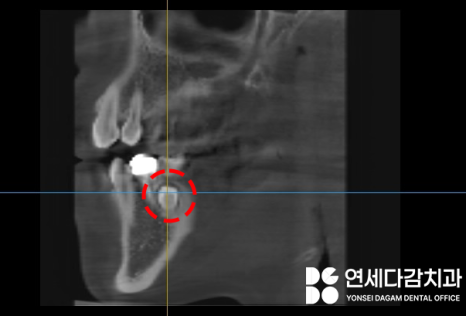

초진 엑스레이(2023.12.18)

오른쪽 아래 작은 어금니 부위에

매복 과잉치가 존재합니다.

(주로 파노라마에서 먼저 발견됩니다.)

올라오지 못한 채로

설측으로 묻혀있었는데,

여기서 문제는

혀의 감각을 담당하는 설신경(lingual nerve)과

제법 가까운 위치라는 것이었습니다.

2023.12.18

연세다감치과 에서 수술 전

촬영한 CT사진입니다.

2차원 파노라마 뿐만 아니라

3차원 CT를 통해

매복된 정도와 위치를 정확하게 파악한 뒤,

주변 구조물이 손상되지 않도록

조심스럽게 뽑는 것이 중요합니다.